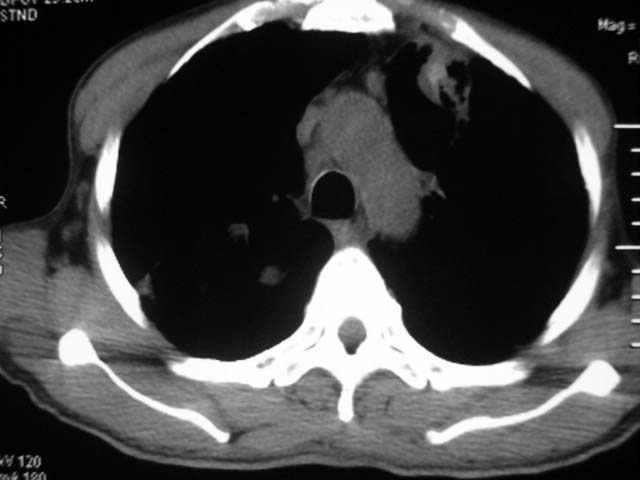

男,52岁,发热2月,糖尿病史。

抗结核治疗irpz方案,血糖未治疗,空腹15.9左右。症状无好转,左胸痛。

复查ct

2、双肺见多发片状及结节状高密度影,大多数病灶中心均见“空泡征”。

3、纵隔内淋巴结肿大。

结果:两肺继发性肺结核并曲霉菌感染。